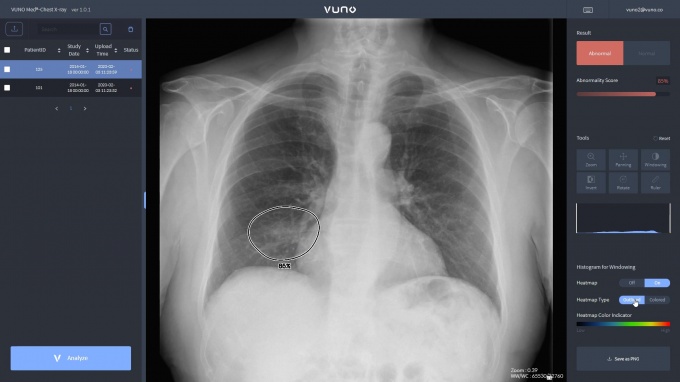

[µ¥Àϸ®¸Þµð ÇÑÇØÁø ±âÀÚ] ÀÇ·áAI Àü¹®±â¾÷ ºä³ë´Â ÃÖ±Ù Áö¿ª ÀÇ·á±â°ü¿¡¼­ Äڷγª19 Áø´ÜÀ» À§ÇÑ Æó·Å °Ë»ç¿¡ ‘ºä³ë¸Þµå ü½ºÆ® ¿¢½º·¹ÀÌ™(VUNO Med®-Chest X-ray™)’ Ȱ¿ëµµ°¡ ³ô¾ÆÁö°í ÀÖ´Ù°í ¹àÇû´Ù.

ºä³ë¿¡ µû¸£¸é ÃÖ±Ù ´ë±¸ÆÄƼ¸¶º´¿øÀ» ºñ·ÔÇØ °­¿øµµ Áö¿ª º¸°Ç¼Ò¿¡¼­´Â Äڷγª19 ½Å°í ´ë»óÀÚ¸¦ È¿À²ÀûÀ¸·Î ¼±º°ÇÒ ¼ö ÀÖµµ·Ï ºä³ë¸Þµå ü½ºÆ® ¿¢½º·¹ÀÌ™¸¦ µµÀÔÇØ Ȱ¿ëÇϰí ÀÖ´Ù.

ºä³ë¸Þµå ü½ºÆ® ¿¢½º·¹ÀÌ™´Â Æó·Å Áø´Ü¿¡ µµ¿òÀ» ÁÖ´Â ÁÖ¿ä ÈäºÎ ¿¢½º·¹ÀÌ ¼Ò°ß 3°¡Áö ¡ã°æÈ­(consolidation) ¡ã°£Áú¼ºÀ½¿µ(interstitia lopacity) ¡ãÈ丷»ïÃâ(pleural effusion)À» ºñ·ÔÇÑ ¡ã°áÀý(nodule) ¡ã±âÈä(pneumothorax) µî ÃÑ 5°¡Áö ¼Ò°ßÀ» °ËÃâÇÏ´Â ±â´ÉÀ¸·Î ÀÓ»ó½ÃÇèÀ» ÅëÇØ ½ÄǰÀǾàǰ¾ÈÀüó Çã°¡¸¦ ¹ÞÀº ÈäºÎ ¿¢½º·¹ÀÌ ÀΰøÁö´É ¼Ö·ç¼ÇÀÌ´Ù.

Çã°¡¹ÞÀº 5°¡Áö ¼Ò°ß ¹× Áúº´¿¡ ´ëÇÑ Á¤»ó/ºñÁ¤»ó ºÐ·ù ¼º´É(AUROC)Àº 99%¿¡ ´ÞÇÑ´Ù.

ºä³ë ÀÌ¿¹ÇÏ ´ëÇ¥ÀÌ»ç´Â “ºä³ë¸Þµå ü½ºÆ® ¿¢½º·¹ÀÌ™´Â ½Ä¾àó Çã°¡¸¦ ¹ÞÀº Á¦Ç° Áß °¡Àå ¸¹Àº ÈäºÎ ¼Ò°ßÀ» 3ÃÊ À̳» ÀÇ½É º´º¯°ú ÇÔ²² Á¤È®ÇÏ°Ô °ËÃâÇÑ´Ù”¸ç “À̹ø Äڷγª19 ´ëÀÀ ½Ã ÀÇ·áÁø ¾÷¹« °æ°¨ ¹× Á¤È®ÇÑ È¯ÀÚ ºÐ·ù µî¿¡ µµ¿òÀ» ÁÙ ¼ö ÀÖÀ» °ÍÀ¸·Î ±â´ëµÈ´Ù”°í ¸»Çß´Ù.